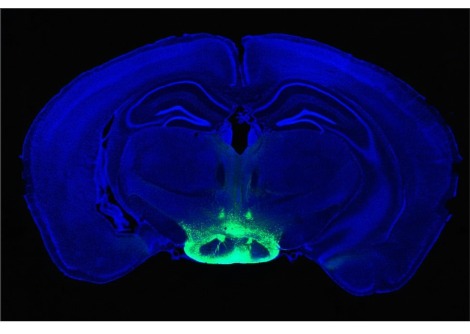

استخدم "تاكيو واتانابي" وزملاؤه من جامعة براون "التصوير بالرنين المغناطيسي الوظيفي" functional MRI لقياس نشاط الدماغ في منطقة تسمى "القشرة الحزاميّة" cingulate cortex أثناء مشاهدة المشاركين لصور الوجوه التي عرضت عليهم. قامت خوارزمية حاسوبية بفرز ردود الأفعال الدماغية للمشاركين في أنماط تتوافق مع الوجوه التي أحبّوها والوجوه التي لم يحبّوها بعد قيام المشاركين بتقييم كل وجه من تلك الوجوه. حاول الباحثون تغيير ردود فعل المشاركين عن طريق تحفيز مهارة نشاط الدماغ في القشرة الحزاميّة.